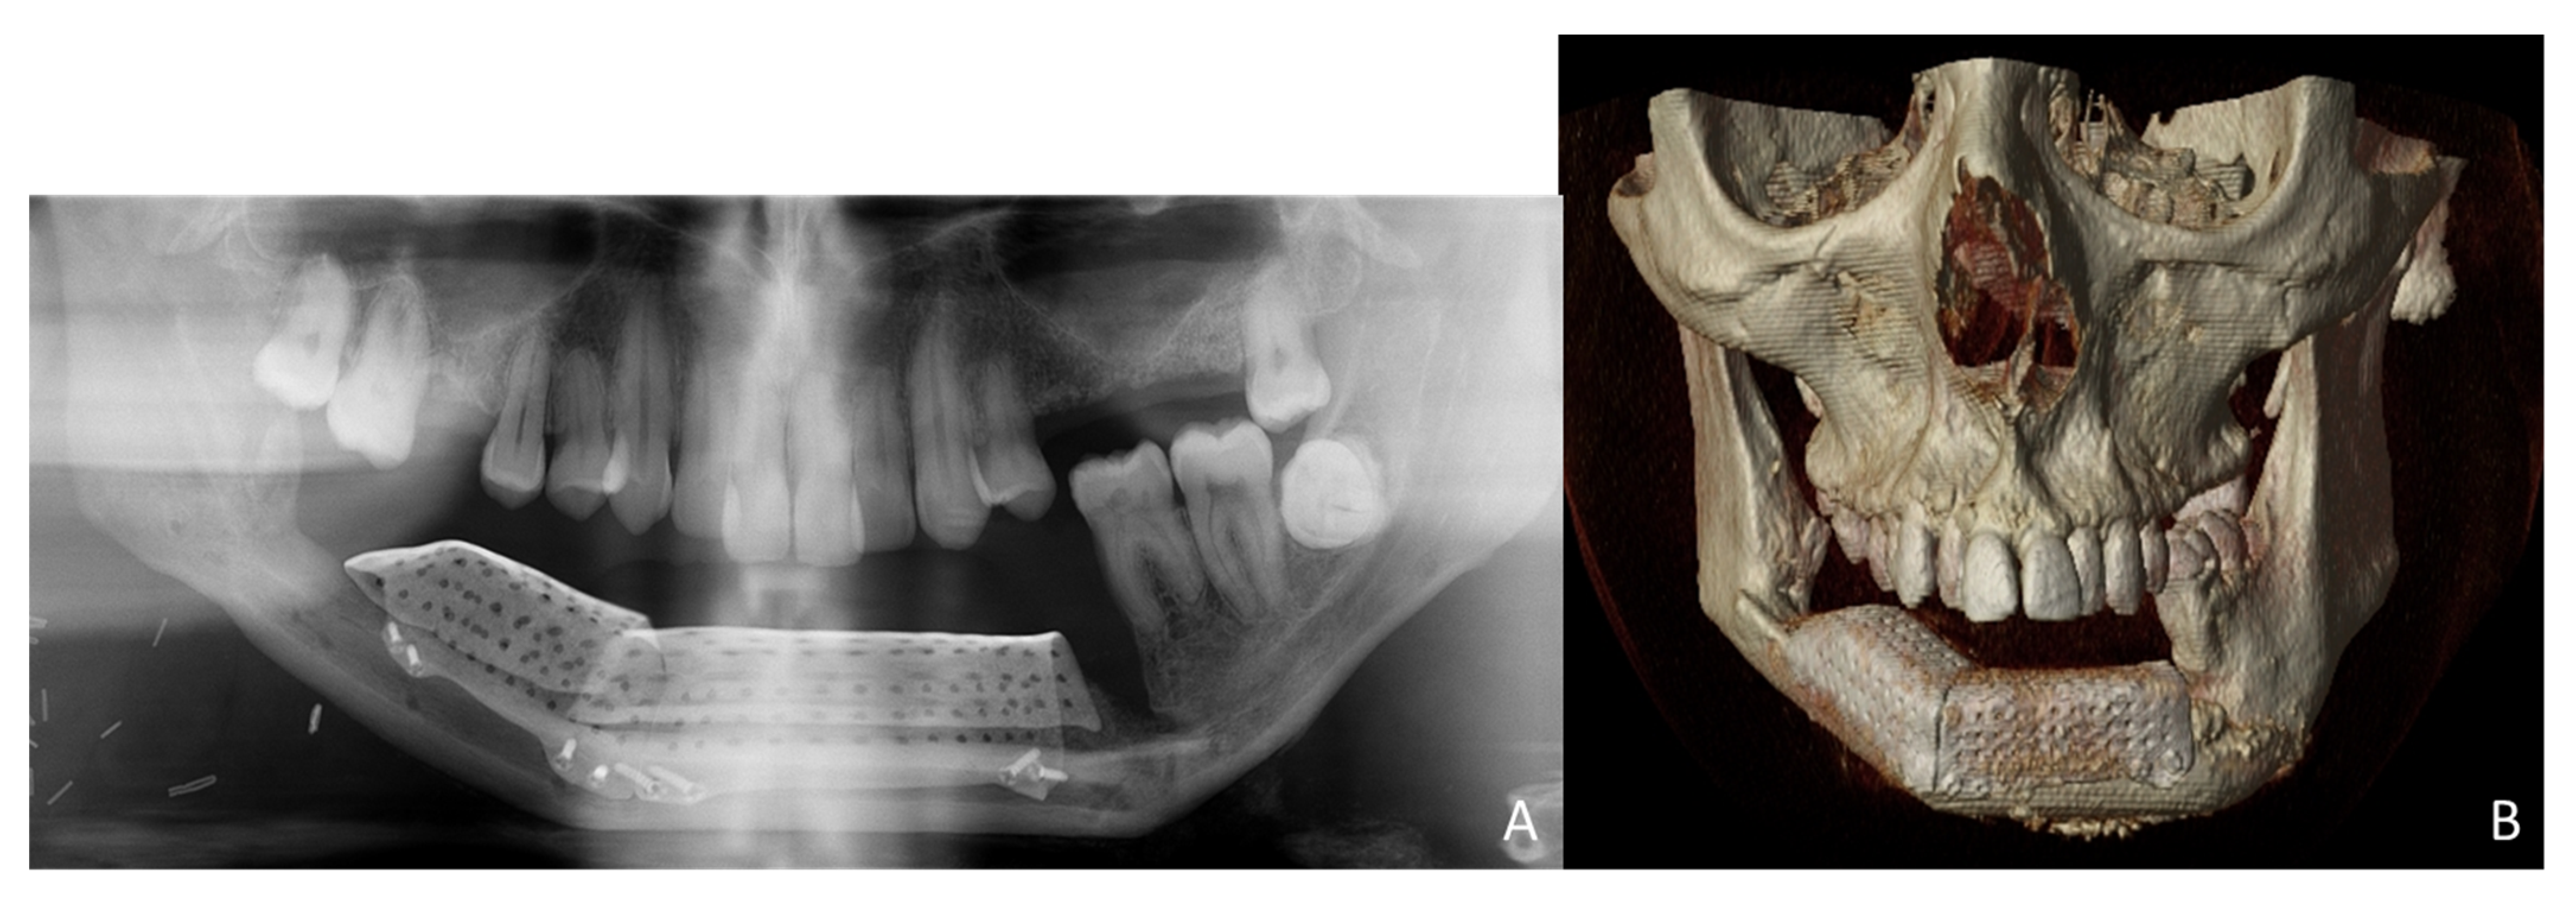

A 38-year-old patient was referred to our Department reporting progressive deformity of the mandibular symphysis with loss of teeth. Panoramic radiography and 3D CT scan showed a lytic lesion with destruction of the external mandibular cortex (Figure 1A).

The patient was diagnosed with a mandibular ameloblastoma, affecting the mandibular symphysis and both mandibular bodies. Tumor resection with segmental mandibulectomy and clear margins, and immediate reconstruction with a two-segment fibula flap was performed (Figure 1B). Six months later, a vertical discrepancy between the remnant mandible and the fibula flap was assessed and a virtual surgical planning (VSP) with a cortico-cancellous iliac crest graft was planned. VSP was performed with the biomedical engineer (Maffinter®, Madrid, Spain) and a three-dimensional virtual reconstruction of the defect was performed with two titanium CAD/CAM meshes (Figure 2) with 1.5 mm diameter pores.

Simultaneously, a cortico-cancellous graft of the left anterosuperior iliac crest was obtained. The graft was fixed to the fibula using the CAD/CAM titanium mesh and 1.5 mm screws (Figure 5B). There was no intraoral exposure of the graft and an increase in the vertical dimension of the fibula was achieved and demonstrated by panoramic radiograph and CT scan (Figure 6A,B and Figure 7A,B).

Figure 6. Postoperative images after 3D reconstruction with CAD/CAM titanium mesh and iliac crest graft. (A) Panoramic radiograph showing the vertical reconstruction of the symphysis and both mandibular bodies with the iliac crest graft. (B) CT Scan with three-dimensional reconstruction of the mandible.